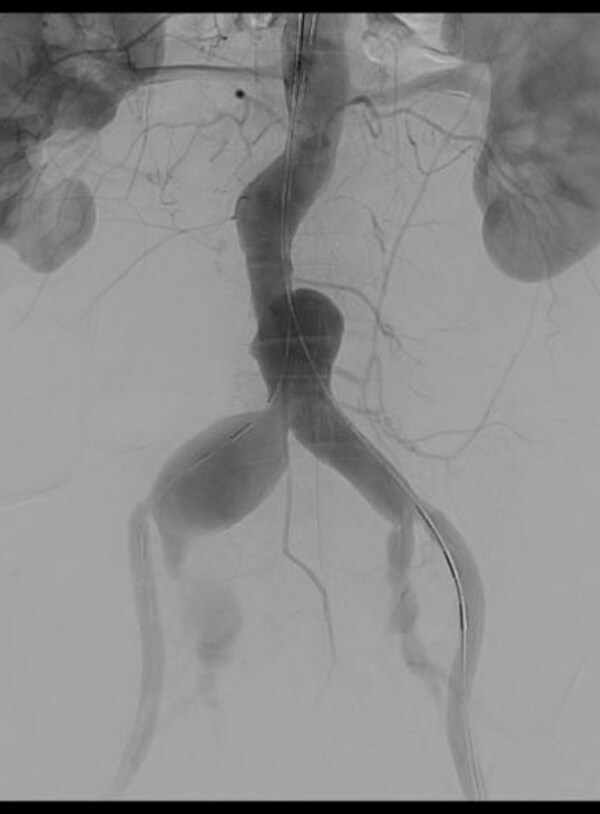

術(shù)前造影

患者腹主動脈瘤及雙側(cè)髂總動脈瘤樣擴(kuò)張,伴有附壁血栓形成,選擇腔內(nèi)修復(fù)治療。又因患者腹主動脈瘤近端伴有潰瘍形成,常規(guī)的腹主動脈支架系統(tǒng)導(dǎo)入可能會遇到極大的挑戰(zhàn)。綜合以上諸多因素,同時考慮到患者年齡較大,全面評估后,黃連軍教授介入團(tuán)隊最終決定通過IBE髂分支支架系統(tǒng)行腹主動脈瘤EVAR手術(shù)。